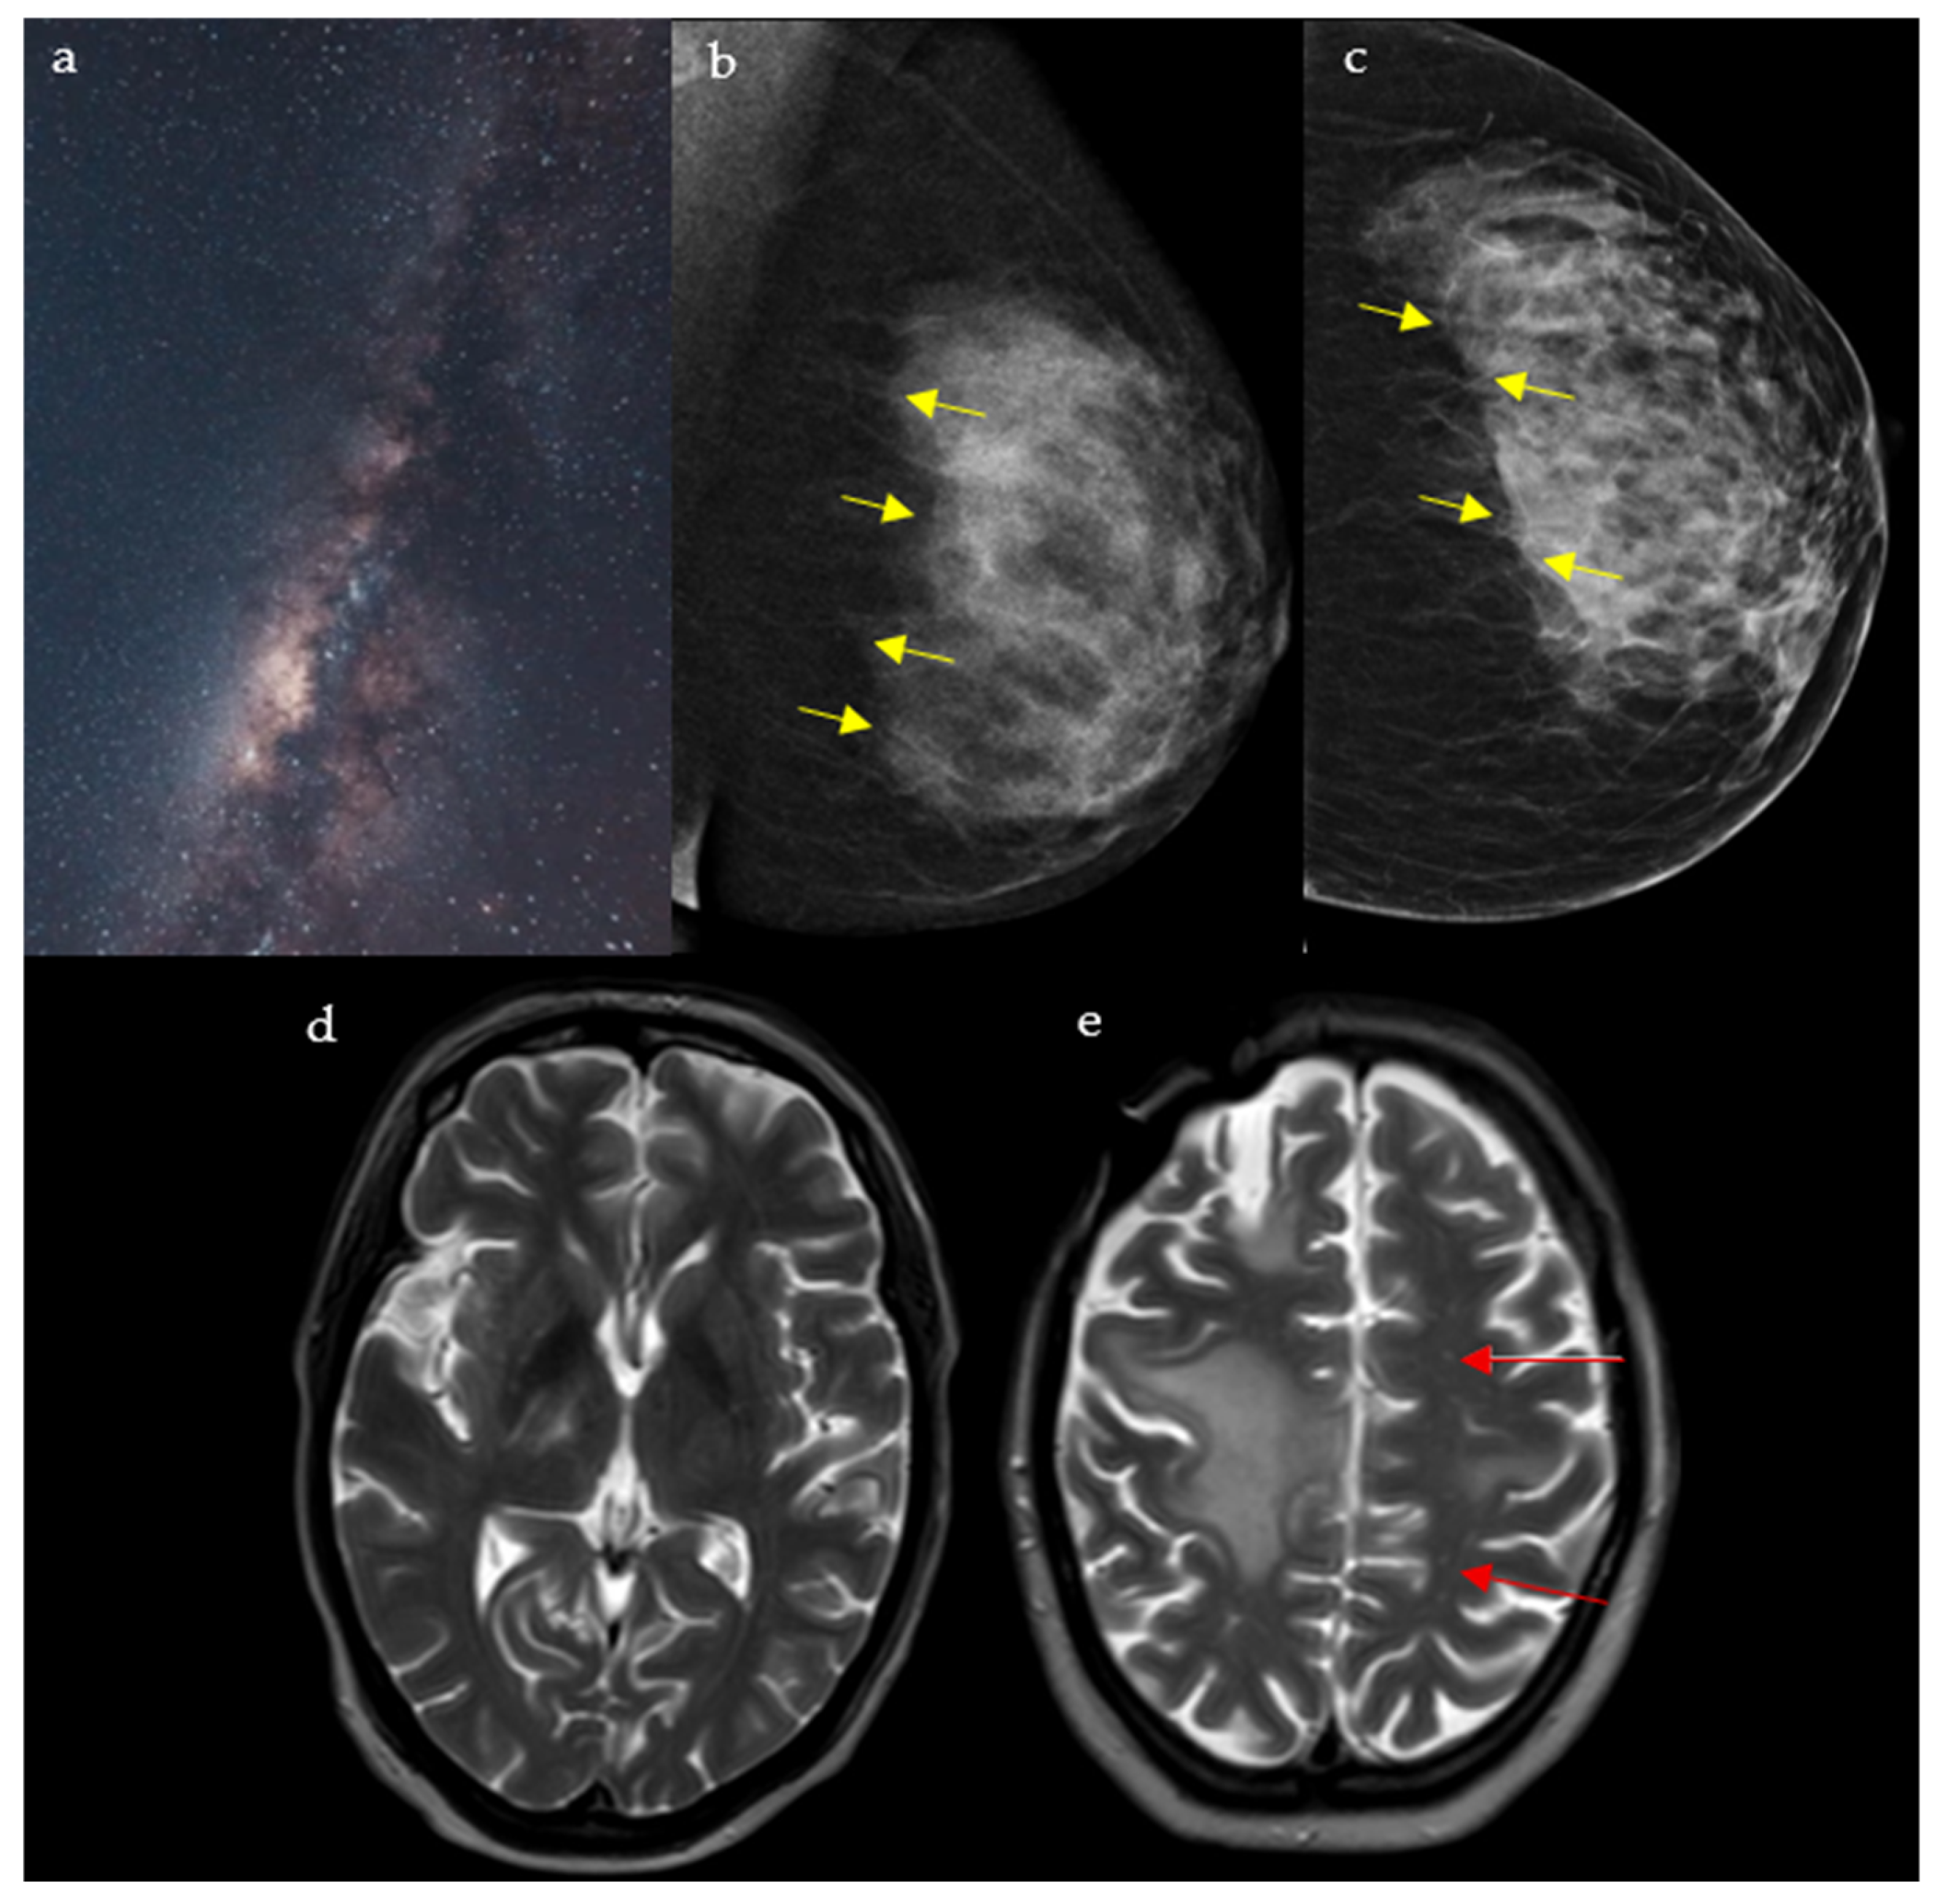

2.5. Milky Way Sign

2.5.1. On Breast Imaging

Mostly detected on breast tomosynthesis, the Milky Way (Figure 5a) pattern is one of the signs that help in the diagnosis of ductal carcinoma in situ (DCIS), the most common type of localized breast malignancy, as well as, less frequently, invasive ductal carcinoma (IDC) and atypical ductal hyperplasia (ADH) [25]. It represented linearly arranged microcalcifications distributed along the non-calcified portions of the lactiferous ducts, which give a hazy background appearance. Multiple fine, punctate calcifications aligned in a linear or segmental distribution on mammography raise suspicion for ductal carcinoma in situ and may prompt biopsy in the appropriate clinical setting. In addition, the “Milky Way” is also the name attributed to the retromammary band of fat coursing parallel to the pectoral muscle seen on the mediolateral oblique (MLO) view of a mammogram (Figure 5b,c) [26,27]. This area deserves particular attention and represents one of the check zones in mammographic interpretation [27].

Figure 5.

A rendering of the Milky Way galaxy as it appears from space (a), resembling the junction between the fibroglandular tissue and the retromammary fat, with an appearance analogous to that of a dark galaxy studded with stars seen on mediolateral oblique (MLO) (b) and craniocaudal (CC) (c) views of the left breast (yellow arrows). The galaxy also resembles the multiple punctate regions of high T2 surrounding the main component of the lesion in PML (red arrows) (d,e).

2.5.2. In Neuroimaging

This pattern is seen in cases of progressive multifocal leukoencephalopathy (PML) on the T2/FLAIR sequence of a brain MRI. It appears as punctate hyperintense T2 lesions surrounding the main PML lesion, hence the resemblance to the Milky Way (Figure 5d,e) [28]. PML is a demyelinating disease of the central nervous system caused by the reactivation of the JC virus, seen in immunocompromised patients [29]. Interestingly, the Milky Way pattern differs in aspect depending on the etiology behind PML: A study showed that it is more frequent in natalizumab induced PML, when compared to rituximab or human immunodeficiency virus (HIV) induced disease [29]. Numerous punctate enhancing lesions scattered around a dominant white-matter plaque are highly suggestive of progressive multifocal leukoencephalopathy in immunosuppressed patients presenting with subacute cognitive decline, motor weakness, or visual disturbances, supporting urgent evaluation for JC virus and immune-modulating therapy.